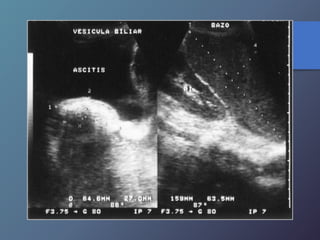

Síndrome de Budd-chiari

• Se caracteriza por la oclusión de las venas hepáticas.

• Esta relacionado con anomalías en la coagulación (policitemia

vera, leucemia crónica, traumatismos, carcinoma renal, chc

primario, embarazo).

• Clínica: Ascitis, dolor en hipocondrio derecho, hepatomegalia y

esplenomegalia.

• Ecográficamente: presencia de liquido (ascitis), aumento en los

diámetros hepáticos y esplénicos, infarto hemorrágico

hepático, aumento de la ecogenicidad en las aéreas infartadas.

• Al Doppler se aprecia aumento del flujo a nivel del lóbulo

caudado e hipertrofia del mismo, incapacidad para visualizar

las venas hepáticas.